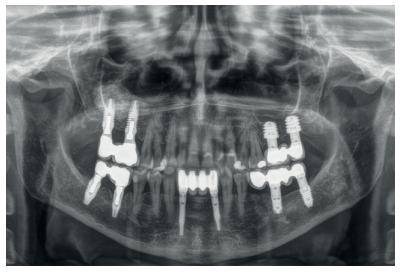

Finally, the stability of both treatments can be seen in the final X-ray at 8 years of age, where both are stable without bone loss (Figure 13).